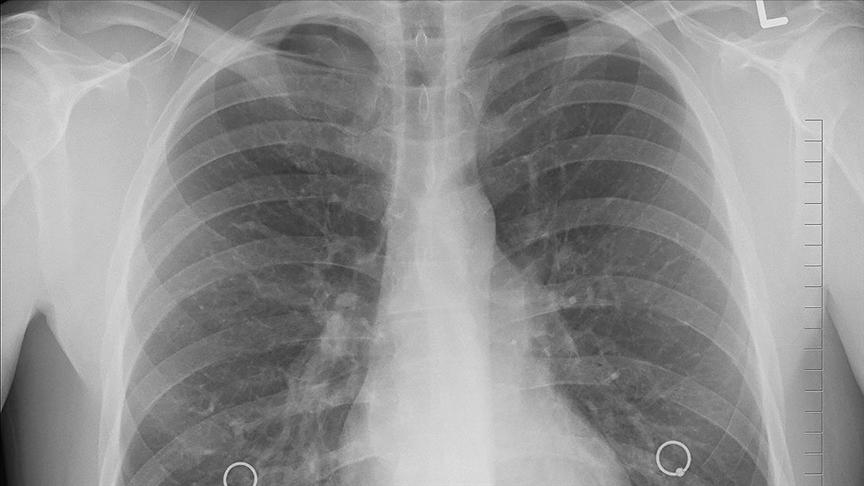

Türkiye'de yılda 35 bin kişi akciğer kanseri tanısı alıyor

Türk Toraks Derneği Genel Başkanı Prof. Dr. İtil, Türkiye'de yılda 35 bin kişinin akciğer kanseri tanısı aldığına dikkati çekerek "Ülkemiz, erkeklerde 100 bin kişide 41,7 oranı ile dünyada akciğer kanserinin en çok saptandığı ülkelerden biri" dedi.

Kanser ölümlerinde ilk sırayı akciğer kanserinin aldığına işaret eden İtil, "Türkiye'de her yıl yaklaşık 35 bin insan akciğer kanseri tanısı alıyor. Ülkemiz, erkeklerde 100 bin kişide 41,7 oranı ile dünyada akciğer kanserinin en çok saptandığı ülkelerden biridir ve akciğer kanserinin en önemli nedeni halen tütün ürünleridir." ifadesini kullandı.